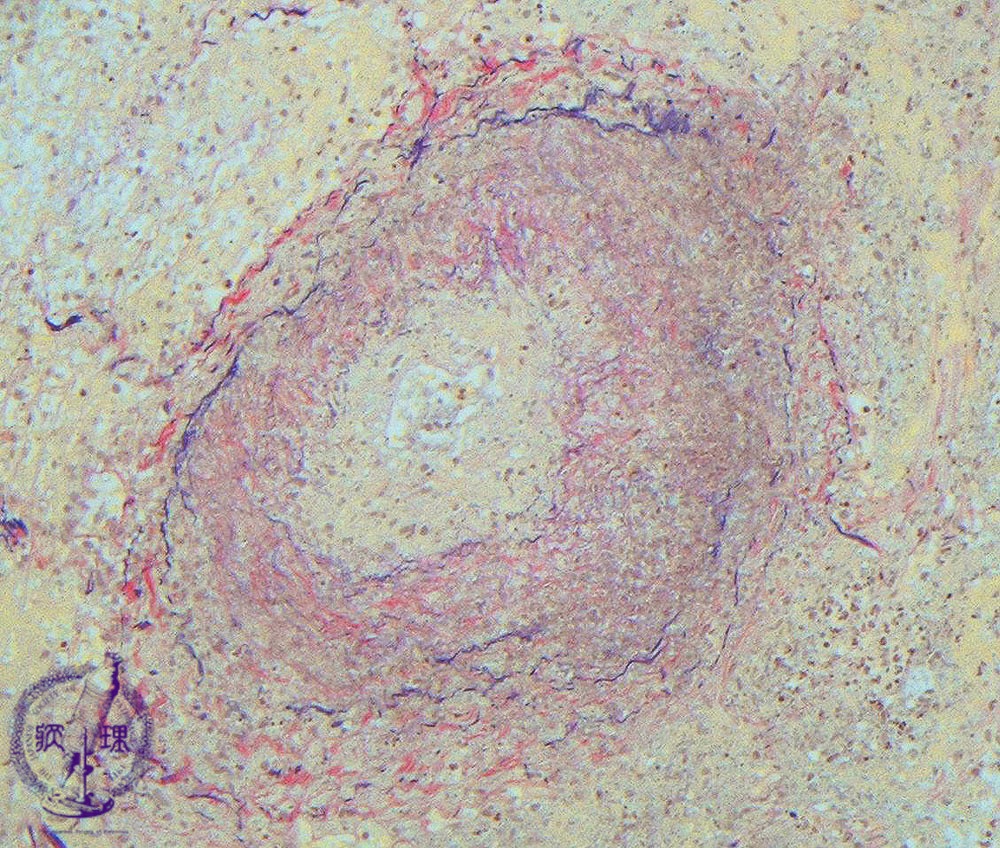

Microscopic view (intermediate power view; EVG staining): EVG stainingdemonstrates the residue of elastic fibers, suggesting necrotizing vasculitis.

Click the image to see the enlarged image.

• There is no guidance by arrows.